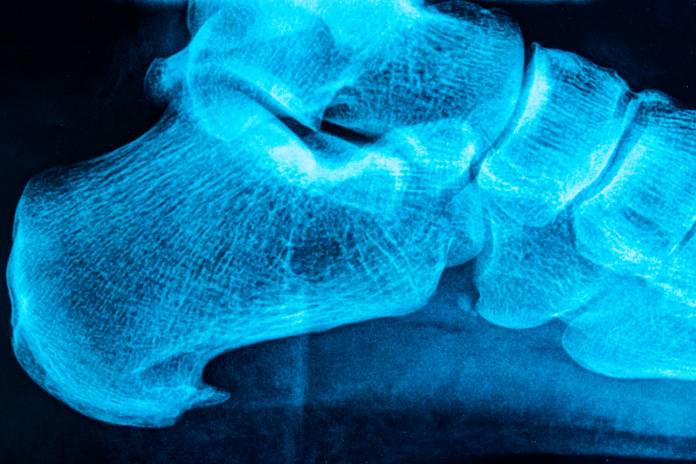

Bei der körperlichen Untersuchung kann der beschriebene Schmerz an der Innenseite der Ferse auf Druck hin ausgelöst werden. Im Folgenden wird noch eine Röntgenaufnahme des Fersenbeines von der Seite aus durchgeführt, um die Diagnose zu sichern. Es kann aber auch vorkommen, dass das Röntgenbild zunächst noch unauffällig ist, obwohl die klassischen Beschwerden eines Fersenspornes schon bestehen. MRT (Magnetresonanz-/Kernspintomographie) und Sonographie werden normalerweise nur aus dem Grund durchgeführt, die Diagnose von anderen Erkrankungen abzugrenzen.